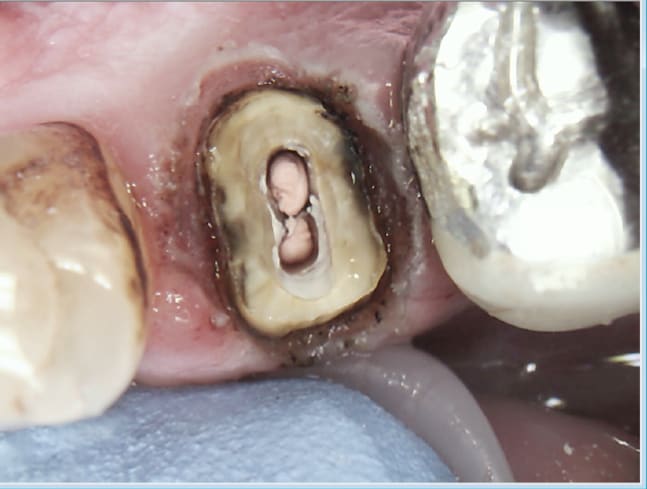

35. Oups ! un SC33 qui s'est barré ! -)))

Le clip flow qui va bien easy à déposer et qui maintient la gencive à distance.....

Je me suis pas foulé sur ce coup là meme pas de RTE à faire . -)